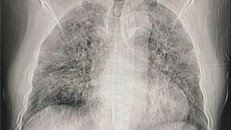

Chụp CT chỉ cho thấy cấu trúc của phổi, nhưng kỹ thuật MRI chuyên biệt có thể cho thấy tình trạng hoạt động của cơ quan này. (Ảnh minh hoạ)

(Ngày Nay) - Theo một nghiên cứu mới đăng trên tạp chí Radiology, một số người đã bình phục sau khi bị viêm phổi do mắc COVID-19 đã có kết quả chụp cộng hưởng từ (CT) cho thấy các tổn thương ở phổi vẫn còn kéo dài cả 1 năm sau khi có các triệu chứng viêm.